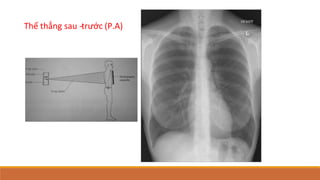

Thế thẳng sau -

‐trước (P.A)

1. Thế thẳng: sau-trước, trước sau

X quang ngực thế sau - trước (PA) là thế được sử

dụng thường qui.